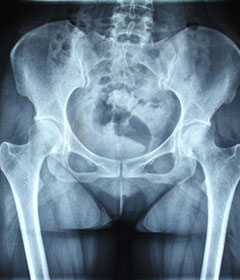

治疗后骶髂关节疼痛消失,腰椎前屈、背伸侧弯活动自如,膝关节无压痛感,复查血沉、C反应蛋白、等各项检查均已达到临床康复的标准。